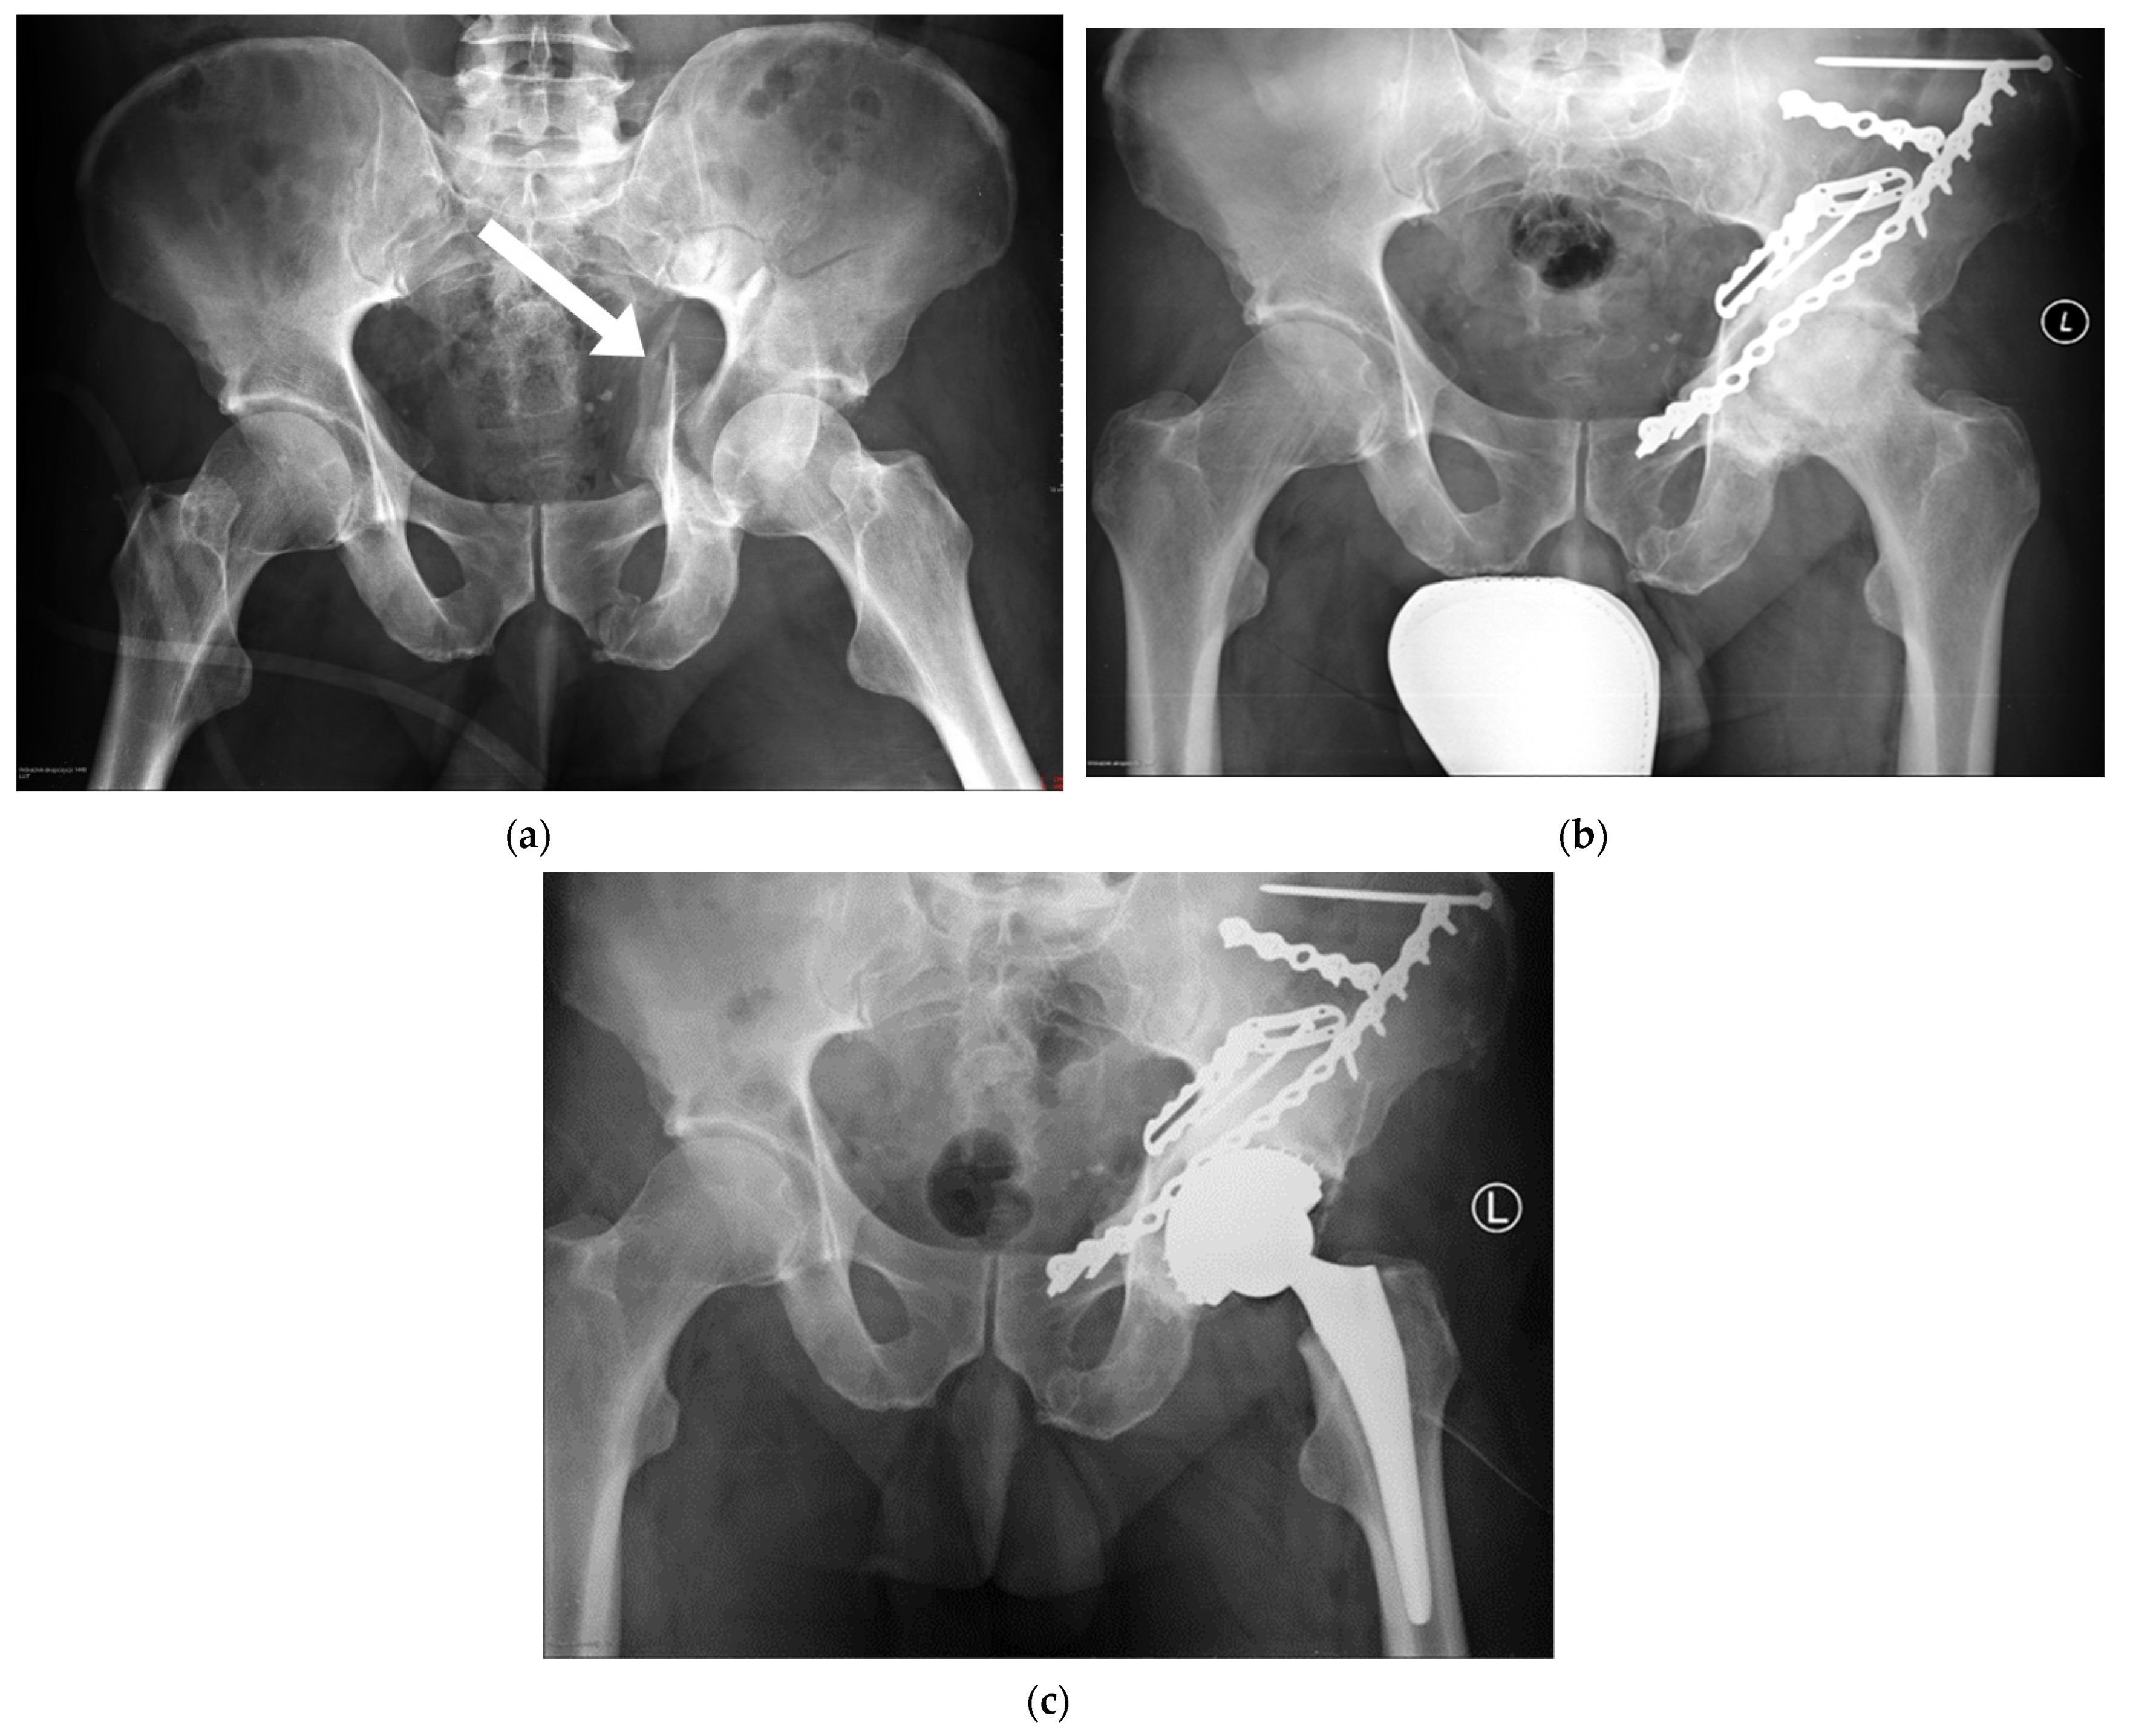

Ijerph Free Full Text Radiological And Functional Assessment Of Treatment Outcomes In Patients After Open Reduction With Internal Fixation Orif Of Acetabular Fractures Html